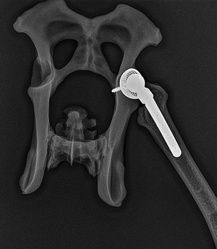

Röntgenonderzoek à vlekkerigheid (botoplosssing) en botnieuwvorming tot en met volledig

vervormde heupkop is mogelijk.

Operatie: heupkopresectie.

Dit is het operatief verwijderen van de heupkop. De operatie is in wezen eenvoudig en complicatieloos. De hond mist nu wel het (overigens pijnlijk) draaipunt van het achterbeen, maar de uitgebreide dijbeenspierophanging van de hond vangt dit uitermate goed op. Snelle revalidatie met zeer goede resultaten is mogelijk.